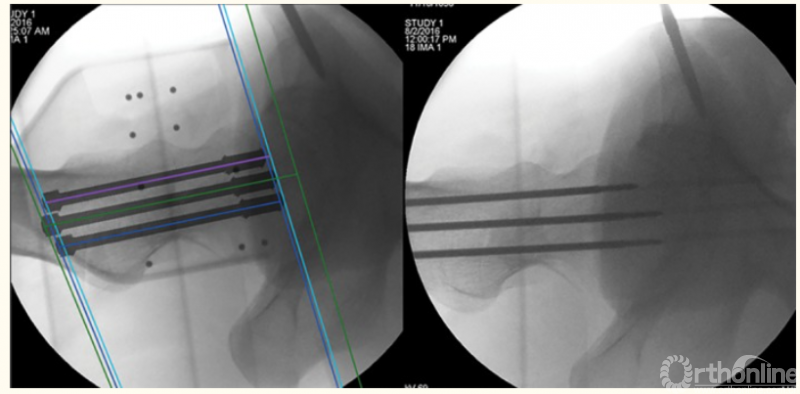

2、骨盆髋臼骨折的机器人辅助手术

3、股骨颈骨折的机器人辅助手术